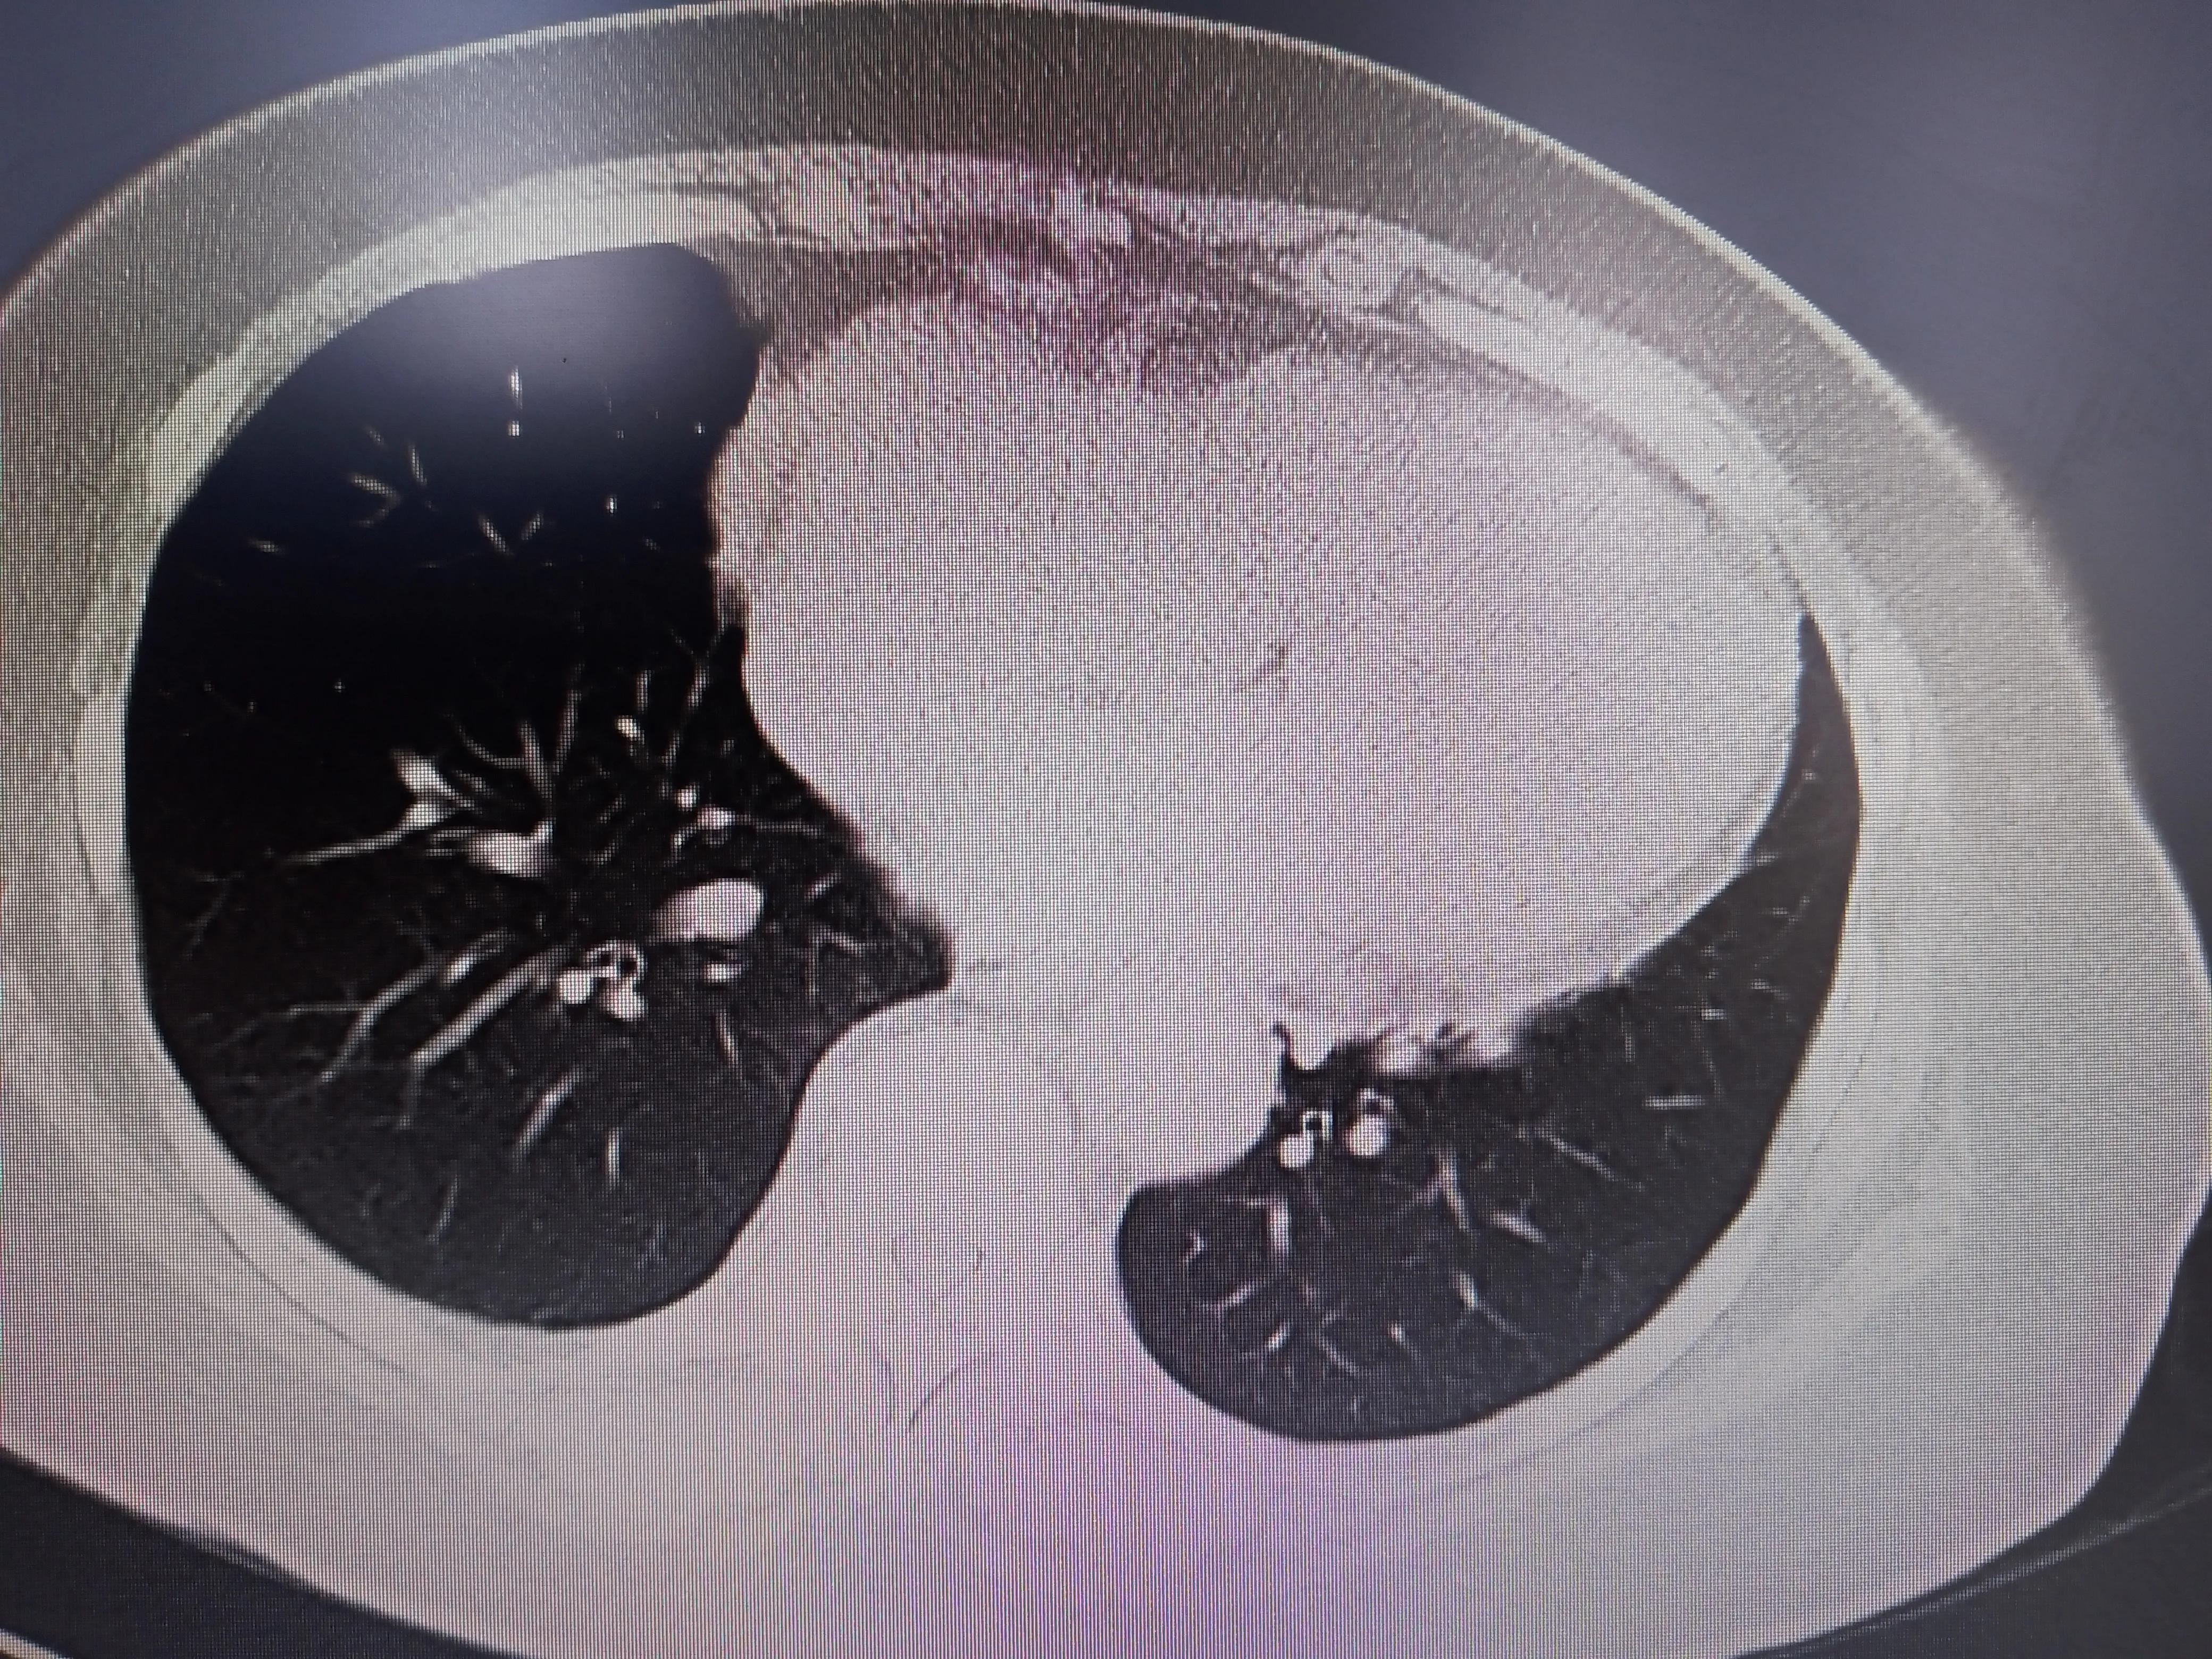

体检可基本排除膈肌麻痹,做了肺静脉CT,排除了肺静脉狭窄或闭塞

同时肺静脉CT里面发现肺里很干净,没有结节也没有明显的急性或慢性炎症;右心明显扩大导致心尖上翘。

右心明显扩大,肺挺干净的